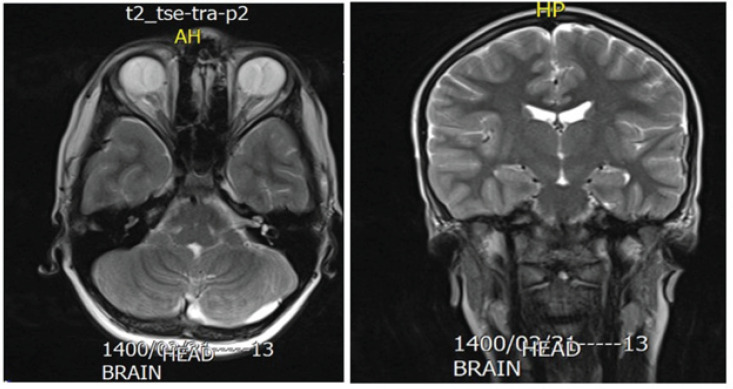

COVID-19 can cause a wide range of ocular manifestations. The most common ocular manifestation is conjunctivitis. Neuro-ophthalmic presentations of COVID-19 are rare. Case reports suggest that COVID-19 infection can cause cranial nerve palsy, including nerves that regulate ocular movements. The present studypresented a case of fourth nerve palsy in a healthy and asymptomatic COVID-19-infected child. A healthy 10-year-old boy was referred to our eye clinic with a complaint of recent abnormal head posture and squint. His past medical history was unremarkable, and he had not received any medication or vaccinations within the last few weeks. No history of ocular or head trauma was observed. The patient was afebrile and had no respiratory symptoms. A comprehensive ocular examination was performed. All examinations, including slit-lamp, pupils, eyelids, and optic nerve heads, were normal. In ocular motor evaluations, left eye hyperdeviation was observed. Because of the history of COVID-19 in the mother of the child, he was referred to an infectious disease specialist and was tested for SARS-COV-2 with a nasopharyngeal swab specimen. The test was positive and SARS-COV-2 was detected. In addition, the patient was referred to a pediatric neurology department. Brain and orbital MRI was performed, and it was unremarkable. The post-viral fourth nerve palsy is uncommon, and post-COVID-19 has not been reported before. Clinicians should consider this infection in any recent strabismus in pediatrics. The children rarely complain of diplopia, and a recent abnormal head posture may be a sign of acquired strabismus.